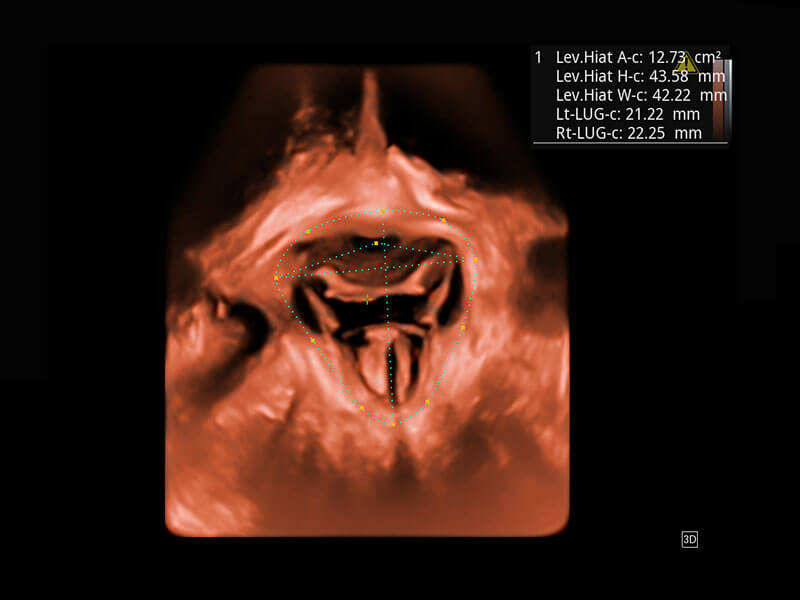

P60為盆底超聲檢查提供應(yīng)用方案,多種腔內(nèi)及腹部容積探頭提供從二維、三維到四維的優(yōu)異圖像品質(zhì),實(shí)時(shí)快速三維容積數(shù)據(jù)獲取,專(zhuān)業(yè)的測(cè)量工具包等人性化設(shè)計(jì),為超聲醫(yī)生診斷提供有力保障。

Lev.Hiat A-r: 16.33 cm2

Lev.Hiat H-r: 53.70 mm

Lev.Hiat W-r: 43.96 mm

Lt-LUG-r: 24.16 mm

Rt-LUG-r: 19.94 mm

能夠簡(jiǎn)化盆底檢查的操作流程,可在二維模式及三維成像模式下實(shí)現(xiàn)一鍵自動(dòng)提取出標(biāo)準(zhǔn)切面、自動(dòng)識(shí)別當(dāng)前切面、自動(dòng)測(cè)量,提升盆底檢查的高效性,同時(shí)也能讓青年醫(yī)生快捷的獲得準(zhǔn)確的檢查結(jié)果。